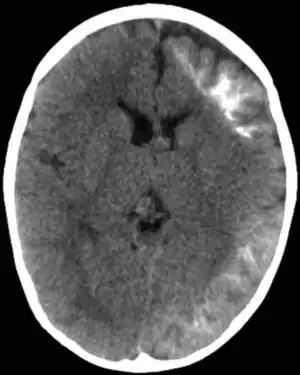

Tomodensitométrie d'un syndrome de Sturge-Weber

• Apparition de calcifications en volutes moulant les circonvolutions cérébrales chez l'enfant (rarement chez le nouveau-né ou le nourrisson).